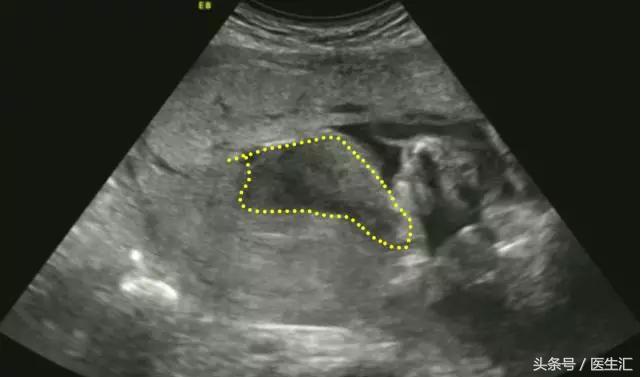

1.胎盘剥离早期:胎盘与子宫壁间见边缘粗糙、形态不规则的液性暗区,其内可见散在斑点状高回声、不均质低回声或杂乱回声,有时为条带状回声(见图6黄色圈内)。有时胎盘后无明显血肿声像,仅有胎盘异常增厚(注意对比历史报告),呈不均增强回声。

(图6)